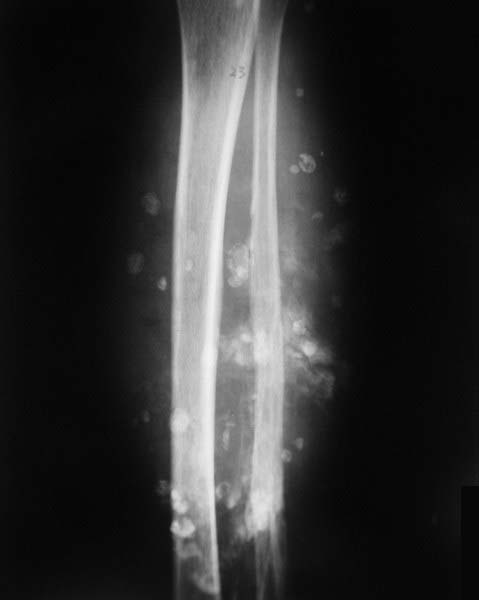

以下是引用余辉在2009-3-12 15:52:00的发言:[br]小腿软组织内见多量“按扣”样及团块样高密度影,为软组织内钙化影,多为静脉石,考虑软组织血管瘤可能,建议ct检查

以下是引用随光逐影在2009-3-12 16:52:00的发言:[br]考虑小腿软组织内血管瘤。